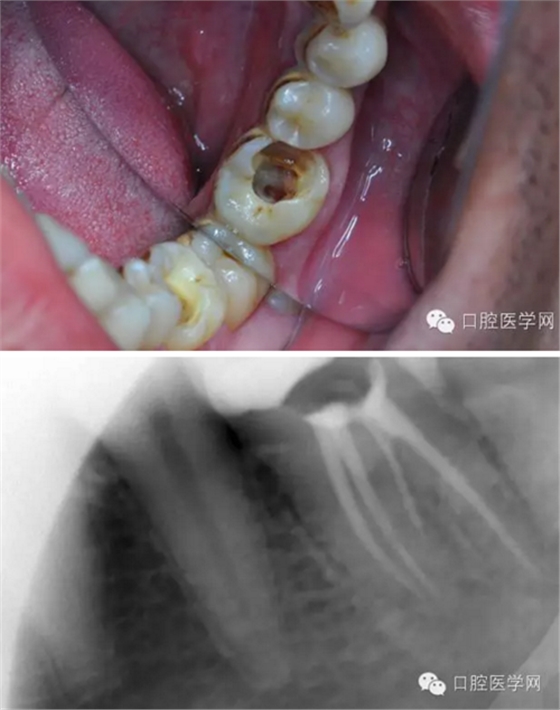

下面我來分享一下我近期的一個鈣化根管病例:

患者,肖某,男,32歲,#36慢性牙髓炎。遠(yuǎn)中舌根根尖1/3彎曲而且鈣化不通,我用盡辦法疏通了很久也沒到達WL,(我一直在幻想,要是有超聲系統(tǒng)該多好,可是現(xiàn)實很骨感,我們單位暫時還沒有超聲系統(tǒng)),后來我放棄了,最后的根充片顯示遠(yuǎn)中舌根充填物距根尖端2.84mm,屬于欠填范圍(根管內(nèi)充填物距根尖端2mm以上),其它三根根尖1/3鈣化相對沒那么嚴(yán)重,根充片顯示屬于恰填范圍(根管內(nèi)充填物距根尖端0.5~2mm)。歡迎網(wǎng)友們針對這個病例提出寶貴的建議!